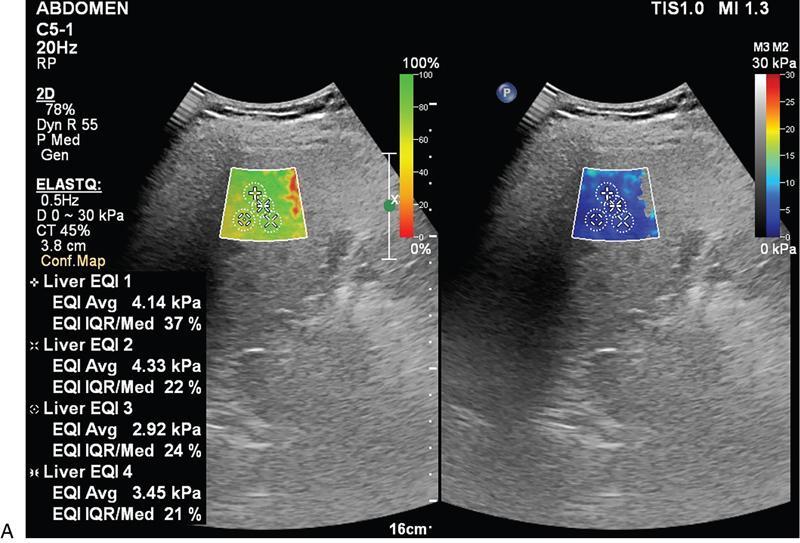

Samarjit Ghuman, Seema Sud, Deeksha Rastogi, Swapnil Sheth, T.B.S. Buxi PLAIN RADIOGRAPHY FOR HEPATOBILIARY IMAGING The diagnostic imaging techniques for hepatobiliary imaging can be intimidating with many techniques/modalities providing the information desired. The job of the diagnostic radiologist includes being familiar with the available choices and pick the ‘best fit’ keeping in mind the pros and cons of each modality, which includes plain X rays, Contrast studies using plain X rays and fluoroscopy, Ultrasound includiojng Doppler and Ultrasound elsastography, CT including multiphase CT and MRI and MRI elastography. Understanding the strengths and weaknesses of every modality as well as the ability to tailor each study individually will help to optimise patient cares. The abdominal radiograph is performed almost exclusively in the supine position and in the AP (anteroposterior) projection. In case of acute abdomen, an erect chest radiograph should also be performed to look for free air under the diaphragm. The standard abdominal radiograph should extend from the diaphragm to the inferior pubic rami, and includes the lateral abdominal wall musculature. Routinely no preparation is required for abdomen radiograph done for hepatobiliary imaging. The radiograph has limited soft-tissue contrast, however, the liver being the largest intra-abdominal organ, casts a perceptible shadow. The margins of the liver can indirectly be seen by outline of adjacent organs like lung, hemidiaphragm, pro-peritoneal fat line, kidney and gas shadows of stomach/colon. The right lobe is seen better than the left lobe of liver. The following pathologies may be visualized on the plain radiograph of the liver. Liver enlargement Liver mass Calcification Increased radiodensity of the liver Decreased radiodensity of the liver An ultrasound is the first line investigation; however, a radiograph may be done for routine evaluation of abdominal pain. The following pathologies may be seen on plain radiograph of the biliary tree. Calculi and Calcifications Gas ULTRASOUND OF HEPATOBILIARY SYSTEM Ultrasonography (USG) is the initial imaging modality of choice for scanning hepatobiliary system. USG is accurate and has high sensitivity and specificity in diagnosing biliary pathologies. Table 9.1.1 shows indications of ultrasound in hepatobiliary system. The real-time nature of ultrasound lends itself to demonstrate mobility of calculi and sludge and the sonographic Murphy sign can easily be elicited during scanning. The main disadvantage is operator dependence, patient’s body habitus, presence of gas which can obscure the visualization of organs, overlying bandages in a postoperative patient and incomplete evaluation in a nonfasting state. USG of upper abdomen should be done after 6–8 hours of overnight fasting. Milk and fatty food should be avoided as they cause contraction of the GB and may cause the GB walls to appear thickened. History of previous surgery, especially cholecystectomy should be elicited. The patient may be positioned in supine or left lateral decubitus position. The GB can be scanned from a high/lateral view, looking through the ribs in supine position or through a sub-costal view in left lateral decubitus position. Position of patient may be changed to demonstrate mobility of structures. The GB is an anechoic structure which is located in the GB fossa along the posterior and inferior aspect of the liver. It has a fundus, body and a neck. It should always be examined in at least two planes (Fig. 9.1.6A and B). The wall of the normal GB should measure 3 mm or less and pathological GB wall thickening can be due to cholecystitis or a neoplastic aetiology. Calculi appear as mobile hyperechoic foci, with distal acoustic shadowing. Other pathologies include polyps and sludge which can be differentiated on the basis of their mobility. The CBD measures less than 6 mm in diameter with increase in the diameter with patient’s age and after cholecystectomy. The CBD is usually scanned in an oblique subcostal plane with the patient in the left decubitus position (Fig. 9.1.7). Dilatation of the intrahepatic biliary radicles is readily assessed with USG and normal intrahepatic biliary radicles are usually not appreciated on USG. Ultrasound of the liver, broadly, is done to assess the size, surface (smooth, coarse or lobulated) parenchymal echogenicity (increased or decreased) vascularity and for presence and evaluation of intrahepatic masses or fluid collections. The liver is divided into right and left lobes by plane of middle hepatic vein which passes through GB fossa and notch of IVC (Cantlie Line). Couinauds classification is the most commonly used system for liver segmental anatomy and described liver into eight functional segments. It is based on distribution of portal and hepatic veins. Every segment has its branch from portal vein, hepatic artery and bile duct (Fig. 9.1.8). Curvilinear transducer (3–5 MHz) is used for routine examination of liver and GB (Fig. 9.1.9). A high-frequency linear transducer (9–11 MHz) (Fig. 9.1.10) can be used to look for subtle irregularity of the liver surface for early Cirrhosis and fine details of GB wall. The liver is scanned in deep inspiration, which causes inferior movement of liver, so that superior borders of the liver are well visualized. Supine position is used for the size of the liver. The measurement is made in sagittal mid clavicular position on right side, in craniocaudal dimension. It is taken from diaphragm to the lower end of the liver. It should be <16 cm and varies with age and sex. The liver is divided into four vertical sectors by three hepatic veins and plane of bifurcation of portal vein divides these 4 sectors in to 8 segments. The right hepatic vein creates vertical plane in the right lobe separating segments V and VIII (anterior) from VI and VII (posterior). The portal vein bifurcation creates a transverse plane and divides these segments into superior (VII, VIII) and inferior segments (V, VI). The left hepatic vein divides the left lobe into medial (IVa, IVb) and lateral sectors (II, III). The left portal vein divides left lobe into superior (Iva, II) and inferior segments (III, IVb). The middle hepatic vein separates medial segments of left lobe (IVa, IVb) from anterior segments of right lobe (V, VIII). Ligamentum teres separates segment III from IVb. Ligamentum venosum separates segment I from IV and II. Cystic duct is an anechoic tubular structure which connects neck of the GB to the extrahepatic biliary tree. In long axis view of GB, the neck of the GB is related to main lobar fissure which appears as a linear echogenic line which runs obliquely between neck of GB and right portal vein. In the right oblique sub coastal view CBD is seen anterior and parallel to portal vein. A series of standardized sections or views may be obtained for liver scanning. Transverse Subcostal View: In this view the probe is angled cephalic and placed transversely under the ribs on the right side and portions both lobes of the liver can be seen (Fig. 9.1.11). Mid Transverse View (Fig. 9.1.12) in this transducer is kept in transverse plane in the midline below the xiphisternum. It visualises the liver in an inferior to superior transverse oblique plane and portions of both lobes of liver can be seen along with right and left portal veins. This view is obtained by angling the transducer superiorly toward the hepatic venous confluence. In this view, we can see the three hepatic veins joining the IVC. Right Parasagittal View for Both Right Lobe and Kidney: This view allows assessment of inferior right lobe of liver. It also allows assessment of relative echogenicity of liver and renal cortex as both are seen together in the same image. Normal liver parenchymal echogenicity is greater than renal cortex and less that renal medulla (Fig. 9.1.14). Parasagittal Right MidClavicular View: In this transducer is kept in sagittal plane in right midclavicular line, and oriented supero-inferiorly. This is the standard view for assessing craniocaudal span of liver (Fig. 9.1.15). Parasagittal View for the Left Lobe: For evaluation of left lobe of liver and lateral segments (2 and 3) (Fig. 9.1.16). This view is obtained along the direction of the main portal vein. CEUS of the liver is done to evaluate Focal Liver Lesions and complements traditional B mode ultrasound and Doppler study. It is a simple, accurate and cost-effective tool complimenting indeterminate CT and MRI findings or for characterization of lesions in patients who cannot receive CT/MRI contrast and can be used in patients with compromised renal function, with minuscule risk of side effects. As CEUS is real-time, microvasculature can be studied along with tissue perfusion kinetics. Indications and uses of CEUS: Contrast agents and technique: Interpretation: Contrast-enhanced ultrasound of a hepatic hemangioma in different phases (Fig. 9.1.19). Limitations of CEUS: Liver elastography is a noninvasive method for diagnosing liver fibrosis. Liver fibrosis is induced by chronic liver disease leading to cirrhosis and liver cancer. Liver biopsy is the gold standard for diagnosing the degree of fibrosis and for staging but it is an invasive method. Elastography helps in analysing the elasticity or the stiffness of the tissue. A stiffer liver tissue indicates fibrosis or chronic liver disease. ARFI is based on the principle of measuring Shear wave velocity. Short duration acoustic pulses which are generated in the tissue and these give rise to shear waves which travel, perpendicular to the ultrasound beam. These shear waves cause tissue displacement followed by recovery. This displacement and recovery depend on tissue stiffness. To monitor these shear waves US beams of low intensity are emitted continuously parallel to the main beam along with the push pulses, and these beams can gather data regarding the tissue stiffness. The shear waves cause tissue displacement and this tissue then recovers from the impulse. From this data the degree of tissue stiffness can be obtained which is displayed either as a map or quantitatively where tissue elasticity is expressed as shear wave velocity measured in meters per second. F0, normal; F1, enlarged fibrotic portal tract; F2, periportal/initial porto-portal septa with intact architecture; F3, architectural distortion with no obvious cirrhosis; F4, cirrhosis. It is also known as Transient Elastography (TE) and works on the similar principle as ARFI, the difference being that B mode ultrasound image is not produced. DOPPLER OF PORTAL VEIN The portal vein divides at the portahepatis into right and left branches. The right portal vein divides into anterior and posterior branches, and the left portal vein divides into medial and lateral branches. Portal vein shows a continuous, forward low-velocity flow (15–28 cm/s) on colour Doppler scanning. The flow is hepatopetal, that is, towards liver and is red in colour as it is flowing towards the transducer. It has an undulating pattern and shows respiratory variation with increase flow in inspiration. It may reflect cardiac variation and shows postprandial increase calibre and flow in healthy individuals. Normal Doppler waveform of portal vein (Fig. 9.1.22). Portal hypertension can be defined as elevated pressure within the portal venous system resulting in impaired blood flow through the liver. INTRAOPERATIVE PANCREATIC AND HEPATIC ULTRASOUND Intraoperative ultrasonography of the pancreas was first described in 1980 by Lane and Glazer. It is an important technique for guidance of both open and laparoscopic surgical procedures of the pancreas. As the transducer is in direct contact with the organ of interest, with no interference with air of adjacent soft tissue, it provides good resolution. It is considered superior to CT and MRI in assessing the intraoperative tumour resectability and vascular invasion and guiding resection. Indications and uses For intraoperative US during open surgical procedures, a high-frequency linear-array transducer or the hockey stick transducer (Fig. 9.1.23) are used which create high-resolution detail of the exposed pancreas. The side-fire curved linear-array transducer is effective for obtaining a wider view of the pancreas and its surrounding structures and for scanning the liver. Intraoperative hepatic ultrasound gives the real-time visualization of the hepatic anatomy and aid for surgical planning and making decision during surgery. Indications and uses Transducer and technique Limitations MULTIDETECTOR CT OF THE HEPATOBILIARY SYSTEM AND CHOLANGIOGRAPHY The cross-sectional plane of the patient is denoted as the x/y plane. The plane along which the table moves is the ‘z’ plane. Multidetector CT denotes more than one detector along the Z-axis, with the latest machines having up to 320 and now even 640 rows of detectors. This provides CT with very fast, high resolution, isotropic images which can be reconstructed in any plane or even curved planes. MDCT scanners can comfortably scan the entire abdomen in 10 seconds or less, thereby allowing visualization of different phases of contrast enhancement. Contrast Media (CM) after administration gets distributed from the intravascular compartment into the interstitial spaces. Intravascular arterial enhancement (for angiography) and parenchymal enhancement have different kinetics. Parenchymal enhancement is directly proportional to total iodine dose being administered and inversely proportional to weight, which is a marker of extracellular volume into which contrast redistributes. Rate of iodine administration has no effect on degree of parenchymal enhancement. As a general rule approx. 500–600 mg of iodine/kg body weight achieves adequate hepatic parenchymal enhancement. For a 60 kg adult, this translates into approx. 100–120 mL of contrast containing 300 mg of iodine per mL. Intravascular or arterial enhancement is controlled by rate at which iodine is administered (flow rate and iodine concentration of CM) iodine flux and duration for which contrast is administered longer injection also leads to better overall arterial opacification due to recirculation effects. This principle is made use of while performing abdominal CT Angiography. Higher iodine delivery rate per unit time using a higher iodine concentration contrast medium also improves conspicuity of vessels and hypervascular lesions such as HCC. For identical parameters, difference in arterial enhancement between patients is dependent on cardiac output with enhancement being inversely proportional to cardiac output. For optimal imaging and enhancement, in multiphase imaging and angiographic studies, contrast material administration and parenchymal or vascular enhancement must be synchronized with CT data acquisition. The two main methods are: Test bolus technique: A test dose of contrast is given and the time to peak enhancement is measured in a ROI placed in a target vessel this information can be used to tailor CT acquisition. Automated bolus Triggering: ROI is placed in target vessel (usually aorta at level of diaphragm) on a plain image. While CM is injected, a series of low dose scans is obtained through the ROI. When the density of contrast reaches a predefined threshold (e.g. 150 HU), at time ‘t’ the scan is automatically triggered. The trigger delay after time ‘t’ is a minimum of 2 sec, and can be programmed to any value. Bolus tracking is nowadays the method of choice for planning contrast medium administration and this technique provides more homogenous opacification. Saline chase is recommended in all multiphase protocols. Significant amount of contrast may be present in the peripheral veins after injection of IV contrast and use of saline chaser leads to better vascular enhancement and lower overall contrast dose (Fig. 9.1.24). Using the above, a standard sequence of acquisitions and contrast enhancement techniques can be tailored to the pathology and organ of interest and pre-programmed into the scanner menu, which includes kVp, mAs, pitch, rotation time, slice thickness etc. This is known as a scan protocol. However, these can be modified as necessary. For example, rotation time can be shortened and pitch can be increased for breathless patients to reduce scan times (Table 9.1.4). Multidetector CT is the workhorse of hepatobiliary imaging. It plays a major role in imaging congenital, traumatic, infective, neoplastic and vascular pathologies of the hepatobiliary system. Scans can be obtained with or without intravenous (IV) iodinated contrast material administration. Multidetector CT scanners are capable of imaging multiple phases at different points of time following injection of contrast and provide dynamic imaging due to fast scan times and rapid coverage of the abdomen. Indications for liver imaging include, but are not limited to: Unenhanced Scan: Hepatic fat estimation, radio opaque biliary calculi. Single Phase Scans: Liver abscess, polytrauma, follow up of known oncologic or benign lesions, abdominal pain, suspected cholecystitis. Multiphase Studies: Evaluation of hepatic masses, imaging in cirrhosis, imaging for resectability, liver donor evaluation, malignancy of GB, hepatic venous outflow obstruction etc. CT Angiography of Hepatic Vessels: Trauma, vasculitis, post-operative bleeding and as a part of multiphase studies. Depending on the indication, scanning protocols can be tailored to highlight the suspected pathology and provide relevant answers for further management (Table 9.1.5). The liver has a dual blood supply, most of which is derived from the portal vein. After injection of contrast, until the portal vein provides recirculated contrast material filled blood to enhance the hepatic parenchyma, the hepatic parenchymal enhancement is relatively poor and dependent only on the hepatic artery. The hepatic arterial phase can be divided into an early arterial phase without any portal opacification, a late arterial or portal inflow phase in which there is some portal vein opacification. This is followed by a portal venous phase in which portal and hepatic veins are enhanced (also called the hepatic venous phase in some articles). In addition, an unenhanced/plain scan and an equilibrium phase can also be acquired. Tumour conspicuity of hypervascular lesions was found to be best on the late arterial or portal inflow phase (Fig. 9.1.25). The early arterial phase is seen up to 10 seconds after trigger, and provides ‘angiographic’ images of hepatic arterial anatomy. This phase is used to provide details regarding arterial anatomy and morphology. Later arterial phase 18–23 seconds, portal venous phase 60–70 seconds and equilibrium phase 180 seconds are obtained after trigger. Equilibrium phase images have been shown to increase detection of hepatocellular carcinoma in cirrhotic patients. The portal venous phase is the standard phase for routine chest/abdomen survey and follow up of hepatic abscesses and hypovascular metastases. Single Phase Scan Protocol: Oncologic follow-up, Liver Abscess – For routine single-phase CT, contrast as per body weight can be injected over 40 seconds and scanning can be done after an empiric delay of 70 seconds from the beginning of injection. This protocol provides good parenchymal enhancement and portal and hepatic vein visualization. Plain scan is optional. Dual-Phase Scan Protocol: Hepatic evaluation in patients with malignancies known to have hypervascular metastases – Neuroendocrine tumours, renal cell carcinoma, thyroid carcinoma, (.) melanoma etc. Late arterial Phase 20–22 seconds and Portal venous phase at 60–70. Plain scan optional. Hepatic Resection Protocol: For patients with known hepatic mass being evaluated for resection. Early arterial phase provides pure arterial or angiographic images. It is obtained at 8–10 seconds post trigger followed by portal venous phase at 60–70 seconds. This is required for arterial and venous anatomy and volumetric evaluation if required. Plain scan is not required. In case a hepatic mass needs characterization as well as resectability planning, late arterial and equilibrium scans may also be done. Indications for angiography are further discussed in the section on angiography. The same biphasic protocol using angiography or arterial phase images is used in patients with trauma suspected to have pseudoaneurysms, hepatic artery thrombosis or dissection in transplant recipients, evaluation of living donors and in patients in whom an angiographic ‘road map’ is required prior to intervention. Triphasic or 4 phase scan Protocol: Standard of care for patients with cirrhosis being evaluated for Hepatocellular carcinoma and for patients being evaluated for hepatic mass of uncertain aetiology. Late arterial phase scan: 20–22 seconds, Portal venous scan at 60–70 seconds and Equilibrium scan at 180 seconds. Plains scans are optional. Our institutional practice is to always do plain scans in patients who have undergone hepatic intervention. Plain scans also help to visualize siderotic and steatotic nodules. A further delayed scan is suggested by some authors at 10–15 minutes for characterization of hepatic masses of uncertain provenance. This is particularly useful in cholangiocarcinoma (Table 9.1.6).

Liver elastography

Two main methods used are ARFI (acoustic radiation force impulse) and fibroscan

Indications and uses

Technique

Scoring system

Liver Fibrosis Staging

Metavir Score

kPa

m/s

Normal

F0

2.0–4.5

0.81–1.22

Normal–Mild

F0–F1

4.5–5.7

1.22–1.37

Mild-Moderate

F2–F3

5.7–12.0

1.37–2.00

Moderate–severe

F3–F4

12.0–21.0+

2.00–2.64+

Limitations of ARFI